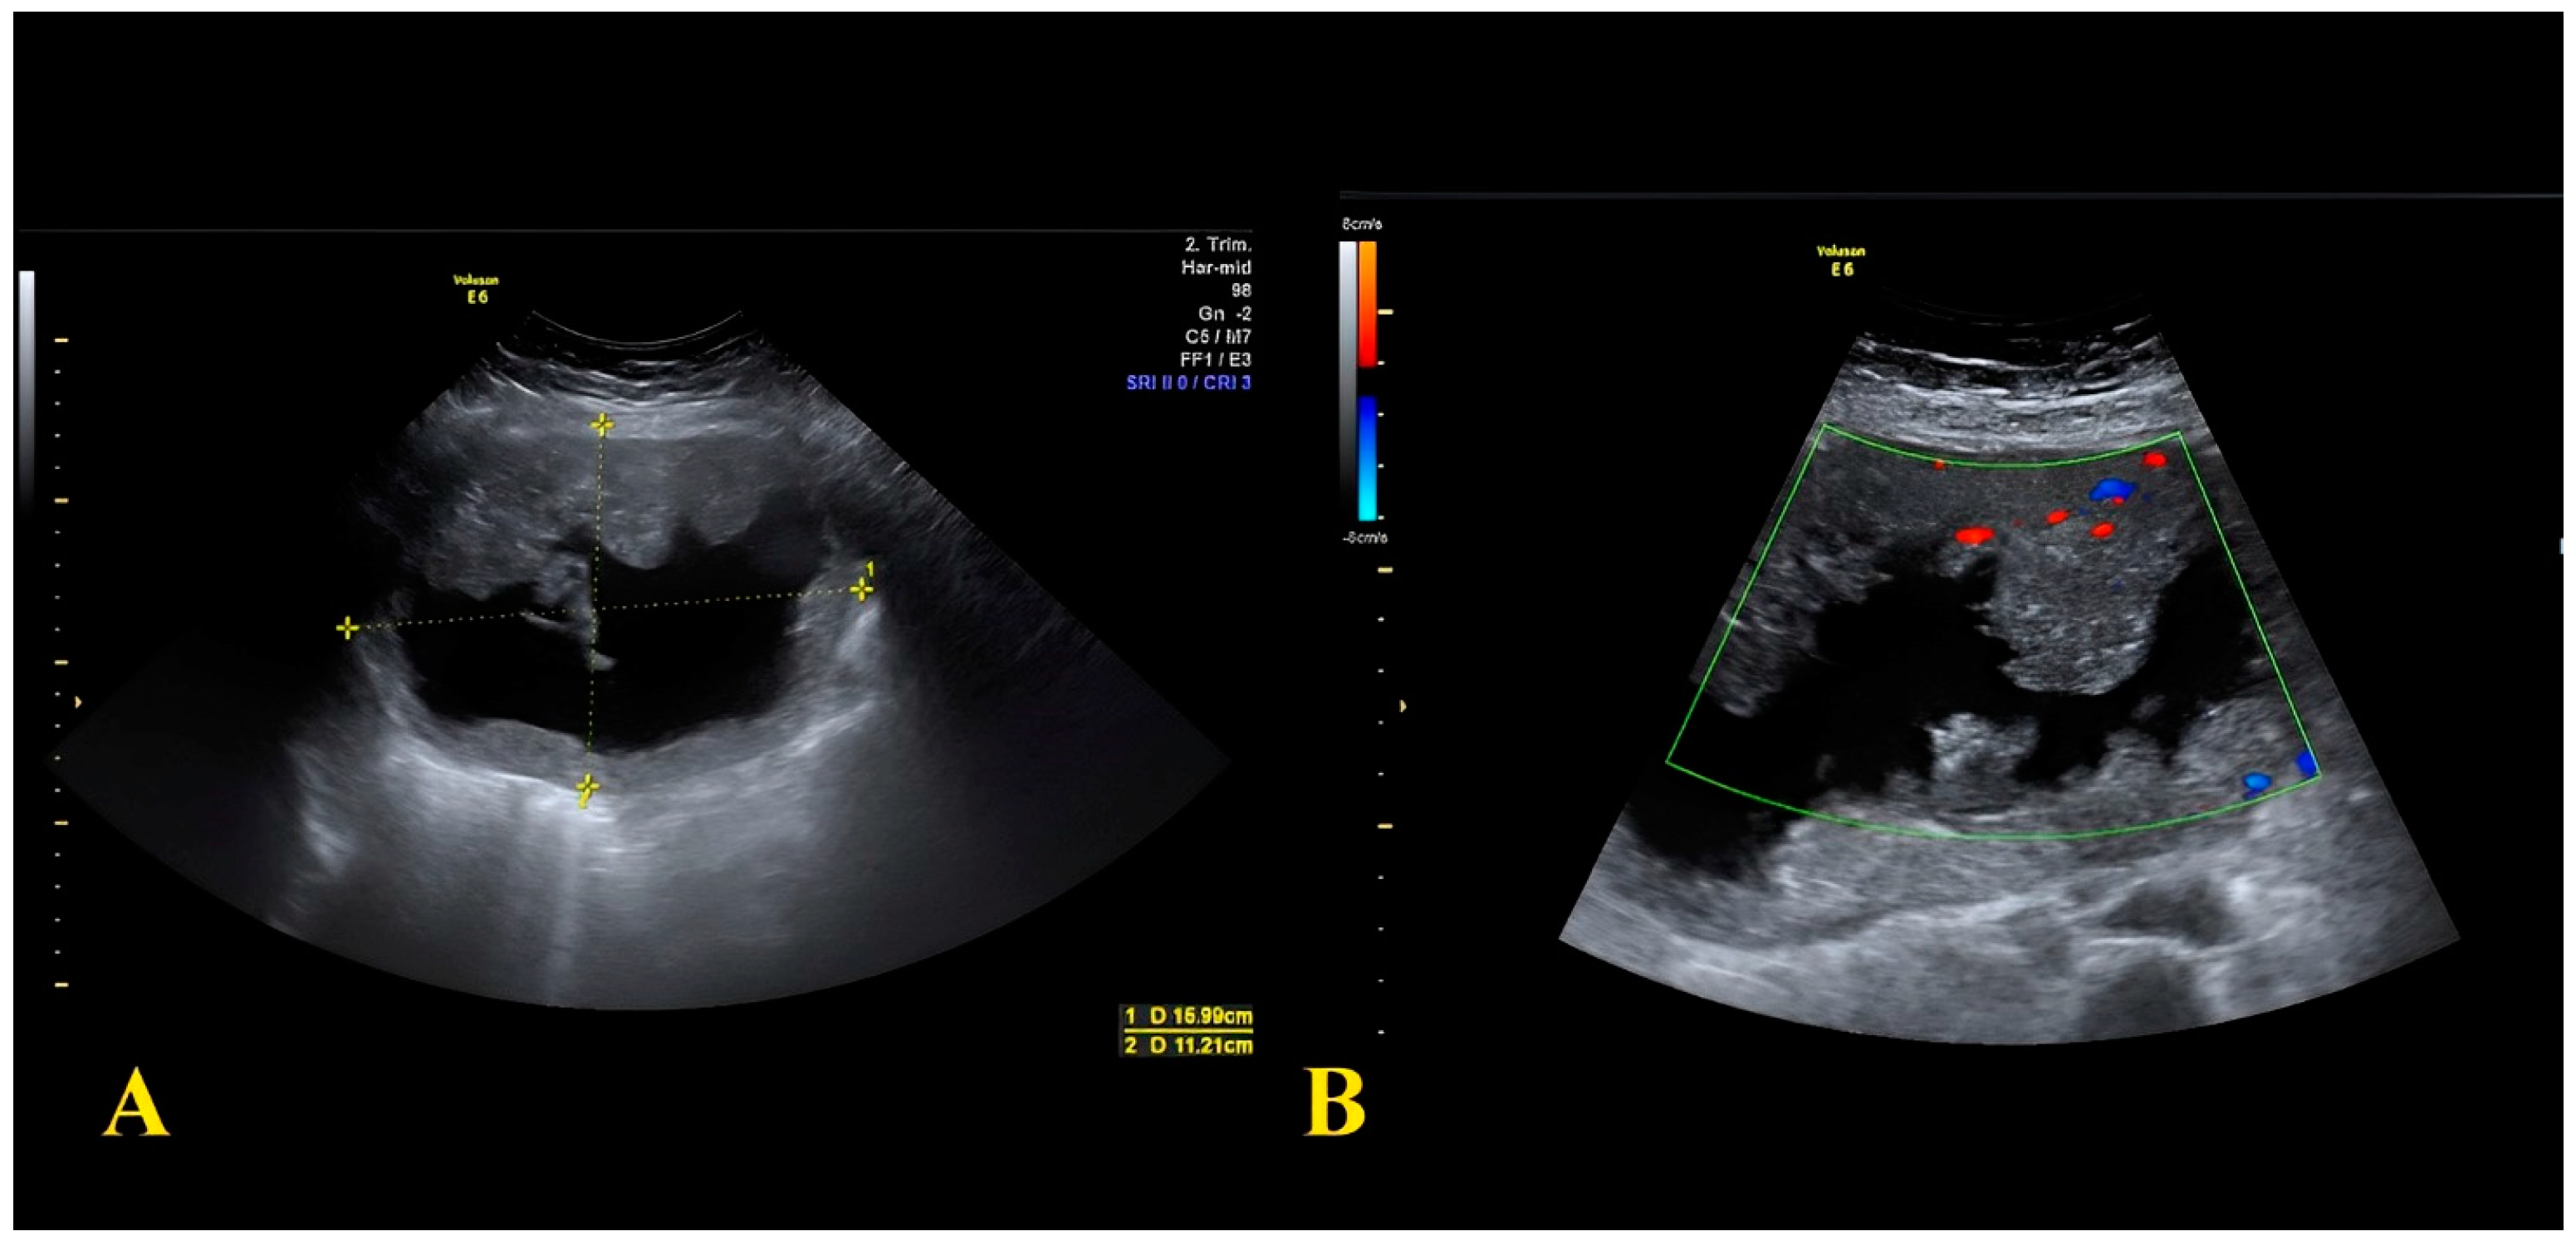

2.1. Case Report 1